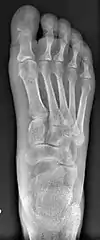

Primus varus deformity is the leaning of the first metatarsal bone away from the second metatarsal and towards the opposite foot (Fig. 1). As it leans over, its head sticks out to form the bunion bump and it also widens the forefoot to cause shoes feeling too tight. Thus when bunion pain becomes unmanageable, surgical correction is to narrow the forefoot by repositioning of the first metatarsal head back to its normal position. This can be done by osteotomy (bone-breaking), soft tissue (non-osteotomy) or fusion techniques.

Syndesmosis procedure addresses specifically the two fundamental problems of metatarsus primus varus deformity that gives rise to the bunion deformity. They are leaning and instability of the first metatarsal bone . Syndesmosis procedure uprights the leaning first metatarsal bone with strong binding sutures between it and the second metatarsal bone (Fig. 2) and then also stabilizes it uniquely by creating a fibrous connecting bridge between these two bones (Fig. 3, 4). First metatarsal bone can be readily realigned because by definition of the metatarsus primus varus deformity its first metatarsal is abnormally loose and mobile.